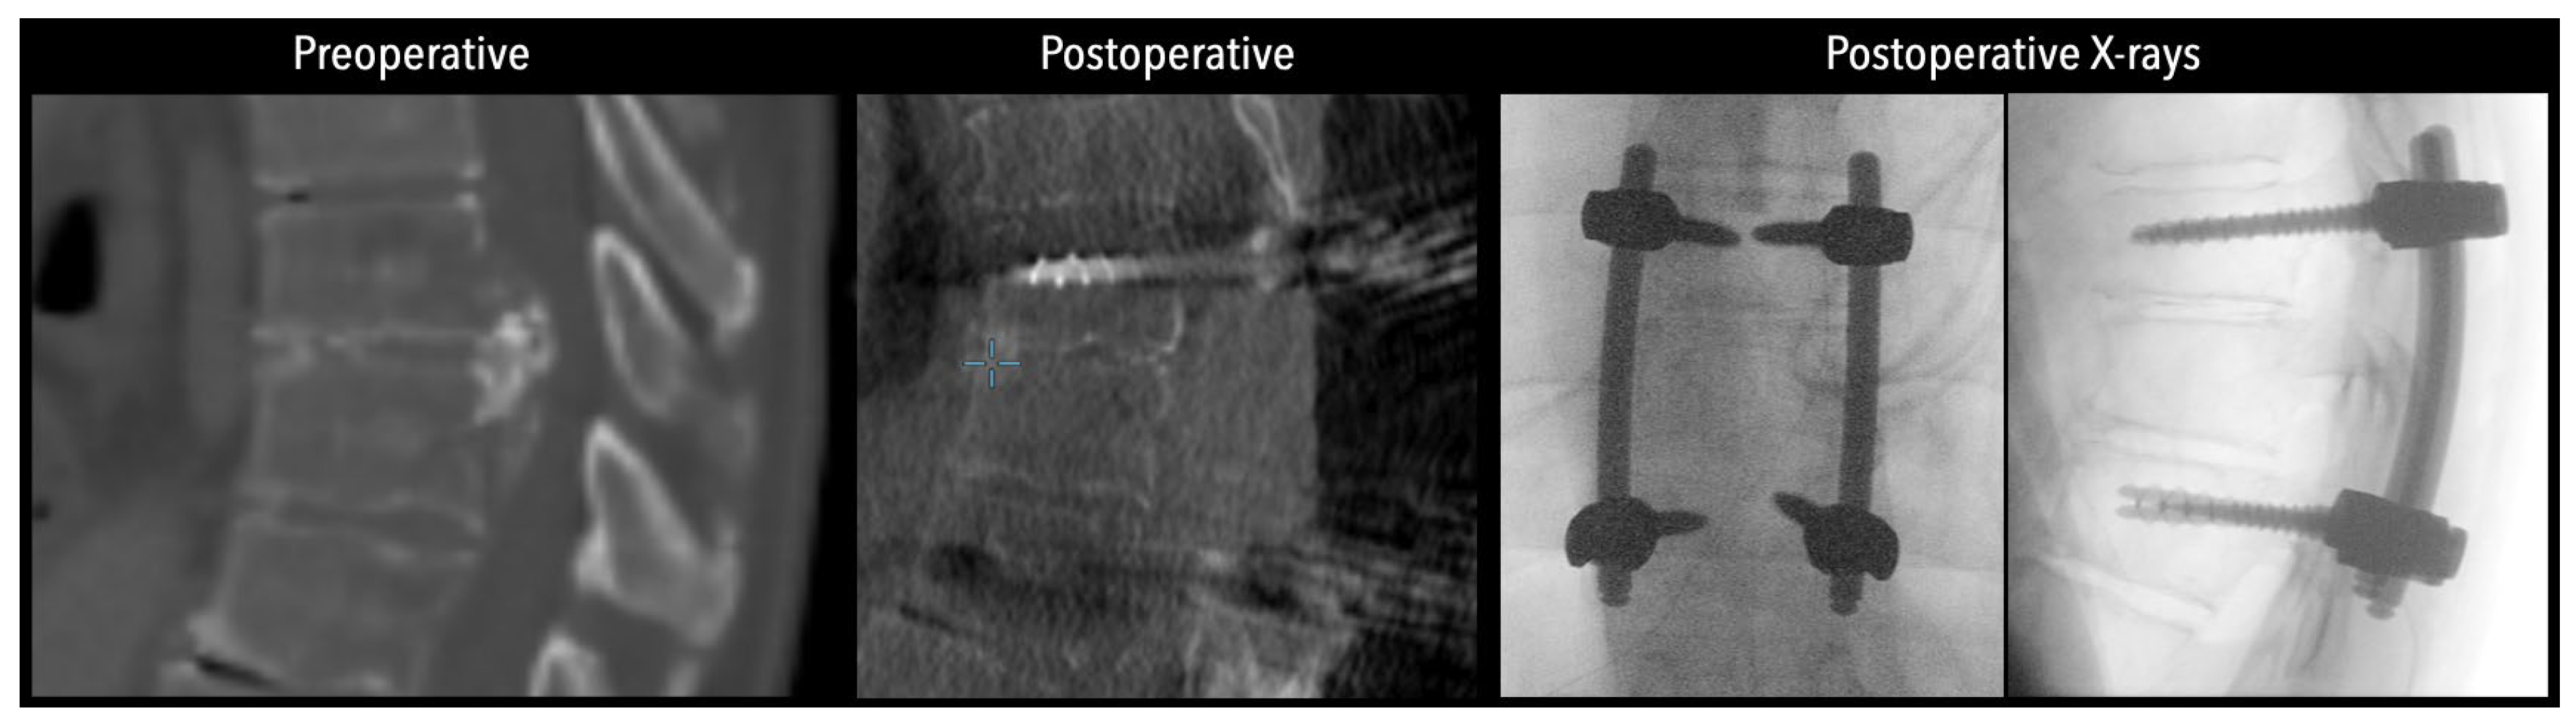

In three of the seven cases, the exiting nerve root at the level of the herniation was ligated due to poor visualization and transected extradurally to improve access. In the remaining four patients, the nerve root was either preserved or dissected intradurally using isocool bipolar diathermy and microsurgical scissors. With gentle medial retraction of the cord under gravity and protection using a micro-patty, the calcified disc was exposed. The ventral dura, when intact, was incised sharply and dissected from the disc surface where possible [Figures 2a,2b,3]. Disc removal was performed using a hockey-stick-shaped Misonix bone scalpel with constant irrigation, guided by intraoperative neuronavigation. The disc material was resected to a depth of 1–2 mm beyond the posterior vertebral wall to ensure adequate decompression. A second O-Arm spin was routinely performed following discectomy to confirm satisfactory decompression, especially given the limitations of the postoperative MRI due to the metal artefact [Figure 4, Figure 5 and Figure 6].

Figure 6. Left side: Comparative pre- and postoperative CT scan of a patient (axial views), illustrating complete discectomy.